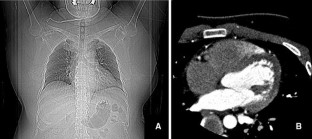

Fig. 1